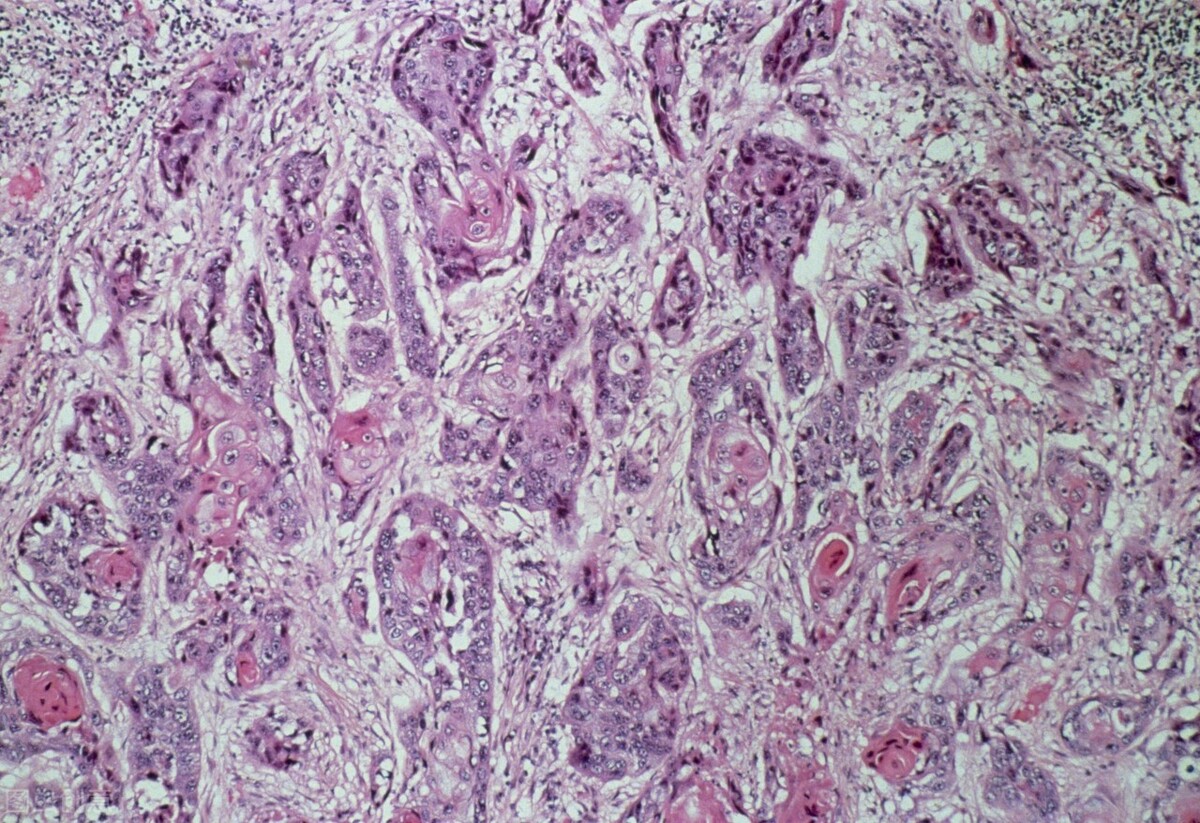

呂先生今年42歲,在2021年秋天開始咳嗽,當時並沒有在意,直到兩個月前,突然覺得胸痛,甚至出現咯血的現象。到醫院活檢的結果是肺鱗癌。

肺鱗癌無法完全治癒,只能儘量延長病人生存期。在全世界的全部惡性腫瘤死亡病例中,肺癌佔19%,居惡性腫瘤死因的首位。肺癌分為小細胞肺癌和非小細胞肺癌,非小細胞肺癌(其中就包括了肺鱗癌、肺腺癌等)手術治療,術後化療或化放療5年生存率為27%,中位生存時間24個月,其中一期、二期病人,5年生存率為38%。

肺鱗癌的位置多數為中央型,通常會容易壓迫到氣管及大血管,故會出現胸悶、氣喘等症狀,若腫塊生長的速度較快,很容易引起血管破裂、出現刺激性乾咳、咯血或痰中帶血的情況,也會有少數患者出現背部疼痛,出現這些症狀時,應儘快去醫院檢查。